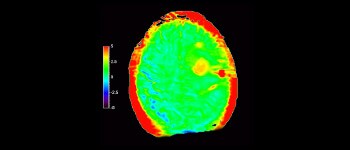

In a society where neurological disorders represent a heavy burden, Philips is committed to provide superb diagnostic clarity and treatment guidance for all patients. Today, although MR is the gold standard in neuro oncology imaging, its accuracy in tumor grading and treatment follow up assessment can be further improved. 3D APT (Amide Proton Transfer) is a unique, contrast-free, brain MR imaging method addressing the need for more confident diagnosis in neuro oncology. 3D APT uses the presence of endogenous cellular proteins, to produce an MR signal that directly correlates with cell proliferation, a marker of tumoral activity. 3D APT can support trained medical professionals in differentiating low grade from high grade gliomas and, in differentiating tumor progression from treatment effect1.